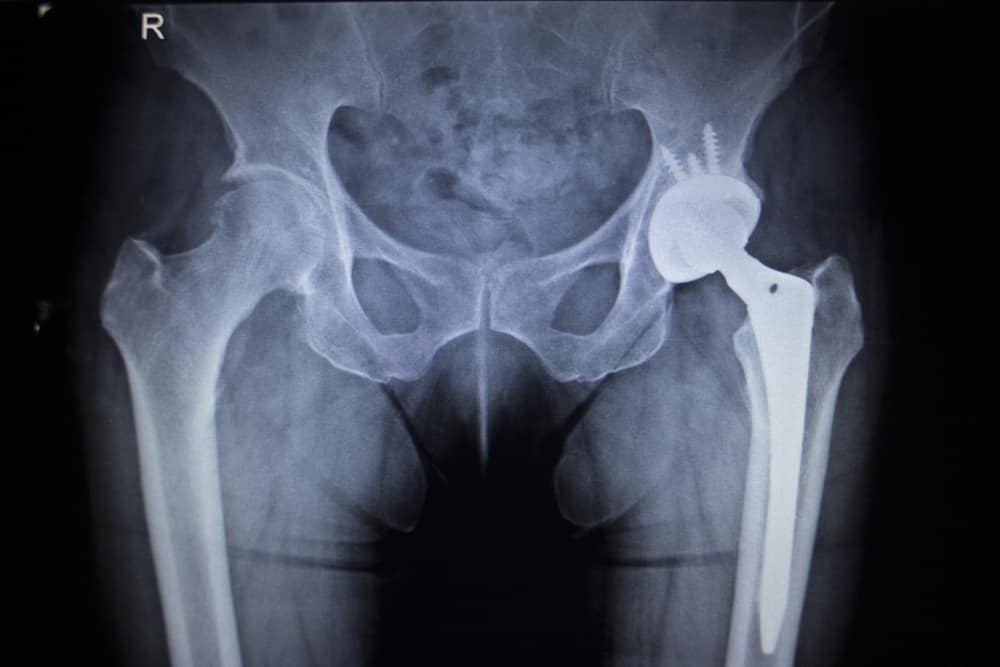

Many of the hip replacement systems sold in recent years were found to contain dangerously flawed designs, which increased the risk of serious complications, including:

- Loosening, disassociation, or fracture of the hip implant

- Metallosis (metal poisoning from implant debris)

- Pain or complications requiring revision surgery

A number of popular hip replacement systems introduced in recent years have been associated with high failure rates and painful complications, often due to design defects and inadequate pre-market testing.

Although artificial hips are generally expected to last 15 to 20 years, some defective designs failed within only a few years, requiring risky revision surgeries and reducing the life expectancy of future implants.

Many types of metal hip replacements have been plagued by reports of early failure, often within a few years after the device is implanted. Amid reports of problems with metal-on-metal hip replacements, several manufacturers have been forced to issue hip recalls or have essentially ceased marketing all metal hip designs due to safety concerns.